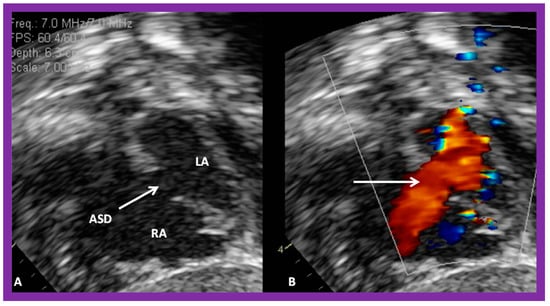

2. Diagnosis

4. Patient Selection for Device Occlusion